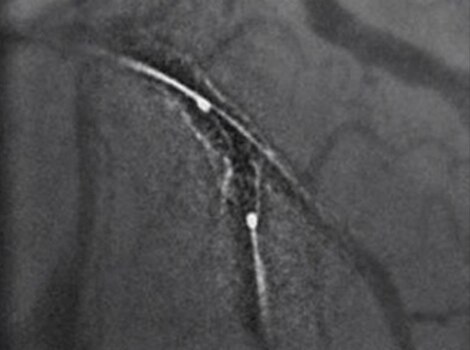

Intervention

For patients sent for revascularization in the catheterization lab, attempts are made to rapidly access the culprit artery and complete further assessment of coronary tree. Rapid intervention can help minimize time to reperfusion from first medical contact.

PCI ASSIST13

Help plan, assess and guide interventional procedures with improved visibility up to 85 percent in moving anatomy. Read More

Successful PCI of the stenotic lesions involves planning, guidance, and assessment of the culprit lesion and assessment of the remainder of the coronary tree.

PCI ASSIST6

Help plan, assess and guide interventional procedures with improved visibility up to 85 percent in moving anatomy.